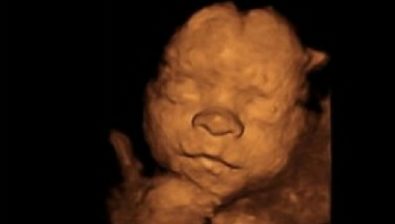

Ultrasound at 26 Weeks

Your baby is practice breathing more and more each day. He/she takes in gulps of amniotic fluid and then pees it back out.

This might sound a little gross, but this is just how babies let their organs “practice,” and it’s completely normal.

If you’re having a boy then his testicles have started to descend, but won’t be fully descended for another two to three months. If you’re having a girl, then she already has a lifetime supply of eggs already inside her.

26 weeks pregnant ultrasound #1 26 weeks pregnant ultrasound #2 26 weeks pregnant ultrasound #3 26 weeks pregnant ultrasound #4